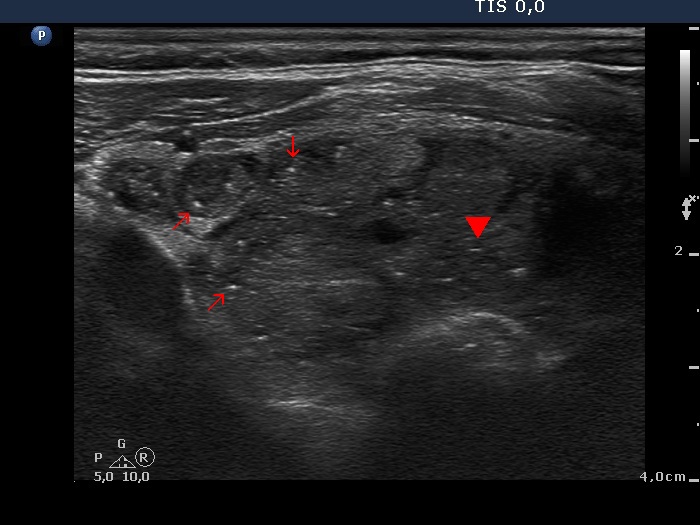

Benign hyperplastic nodule (histological diagnosis) - case cons039

|

Two foci of coarse calcification are presented, one in the left horizontal and another one in the right longitudinal scan.